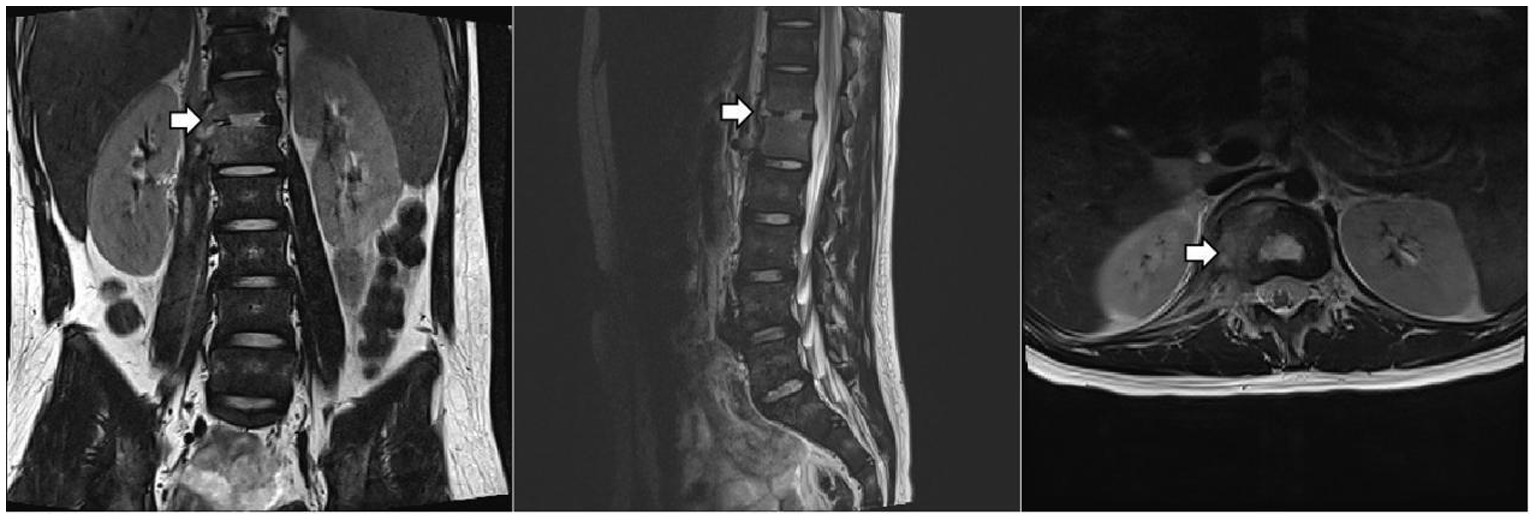

Given the predominance of Gram-positive bacteria in osteoarticular infections, meropenem was discontinued first, after his temperature had remained normal for one week. After two weeks of anti-tuberculosis therapy, repeat thoracolumbar MRI (Figure 2) showed progression of the T12 and L1 lesions. He underwent surgical debridement, and the excised tissue was sent for pathological examination and pathogen identification. The patient developed a fever again after surgery. Laboratory tests showed the following: CBC: WBC 8.1 × 10^9/L, N% 76.4, HGB 125 g/L, and PLT 304 × 10^9/L; CRP 77.9 mg/L. Imipenem/cilastatin was added to cover resistant Gram-negative bacteria.